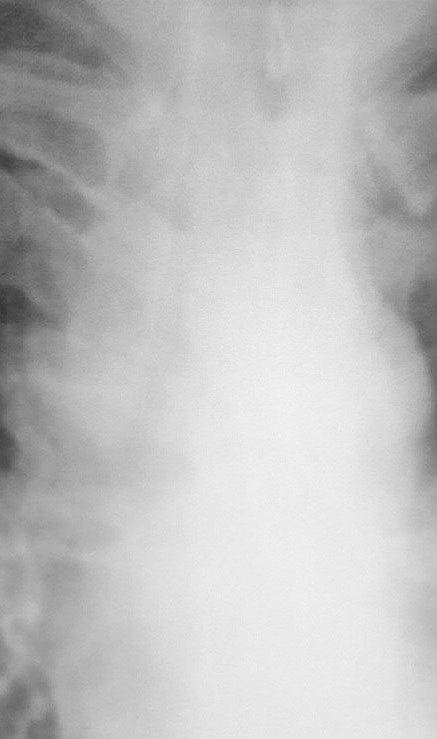

Потупил с диагнозом инфильтр tbs с поражением в/гр и периферич л/у. Болеет около месяца. Не контактен, пов t до 38. Менингиальные знаки 3+. Умер через 30 часов, на вскрытии...

Заподозрить еще как можно. Доказать, проблемно. Но подняв литературу узнал что картина типична для хронического... на фоне которого развивается... Обратите внимание на кисты слева, а справа формируется аналогичная.

Боковая.